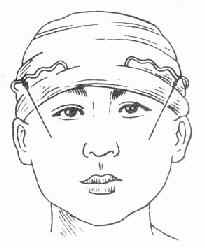

2.牵引复位:颌骨骨折后,经过较长时间(上颌骨三周以上,下颌骨四周以上),骨折处已有部分纤维组织愈合,手法复位不成功,可采用牵引复位法。下颌骨骨折多用颌间牵引,就是在下颌骨有移位的骨折段上安置分段牙弓夹板(图4-16),然后在与上颌的牙弓夹板之间,用小橡皮圈作弹性牵引,使之逐渐恢复正常的咬合关系。上颌骨骨折后,如骨折段向后移位,可在上颌牙列上安置牙弓夹板,在头部制作带有金属支架的石膏帽,在牙弓夹板与金属支架之间作弹性牵引,使上颌骨骨折段向前复位(图 4-17)。需要较大牵引力时,也可作卧式重力性牵引。

| 图4-16 分段式牙弓夹板 | 图4-17 金属支架石膏帽,将上颌骨骨折段向前牵引复 |

5.颅颌固定法:上颌骨横断骨折,不能单纯依靠下颌骨进行固定,可利用颅骨进行固定,否则面中部易发生拉长变形。固定方法是先在上颌牙齿安置牙弓夹板,然后用不锈钢丝一端结扎在后牙区牙弓夹板上,另一端经口腔内穿出颧颊部软组织,悬吊在石膏帽的支架上(图4-22)。同时加有颌间固定。

图4-22 颅颌固定法